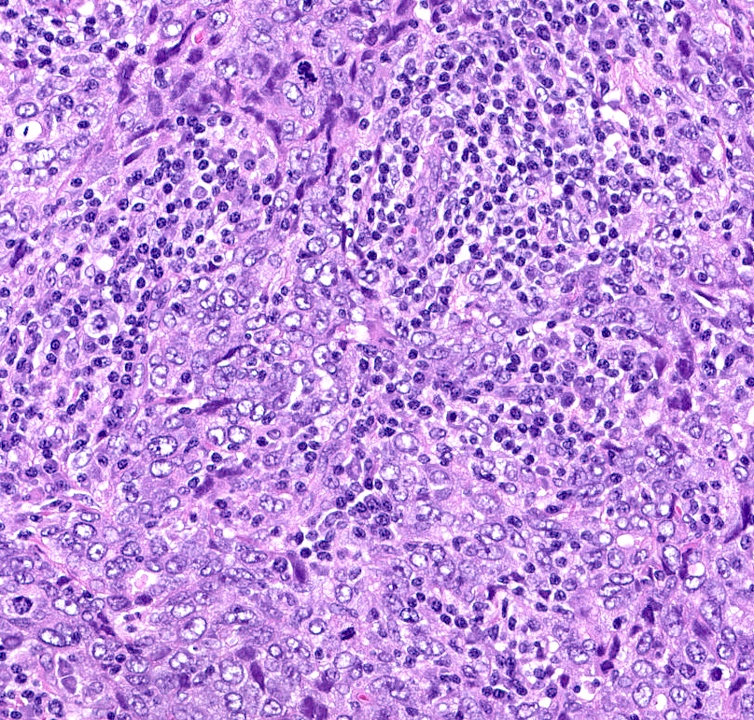

- Basal-like: high grade IDC, NST, solid tumor growth with pushing borders, geographic necrosis, nuclear pleomorphism, brisk inflammatory infiltrate, high mitotic index, high Ki67

A 67 year old woman underwent a partial mastectomy for a breast tumor shown in the image. Microscopic sections revealed a high grade invasive ductal carcinoma growing as a solid mass with pushing borders, areas of necrosis, brisk mitoses and abundant tumor infiltrating lymphocytes. The tumor was negative for ER, PR and HER2 and was classified as basal-like by gene expression profiling. What other immunostain(s) might be positive?

B. EGFR. Basal-like breast cancers are typically high grade invasive ductal carcinoma of no special type that show solid tumor growth with pushing borders, geographic necrosis, nuclear pleomorphism, a brisk inflammatory infiltrate, a high mitotic index and a high proliferative index with Ki67. Most basal-like breast cancers express basal cytokeratins (keratin 5/6, 14, 17) and EGFR. Answer A is incorrect because while a minor proportion of triple negative breast cancers can express androgen receptor, the prototypical AR positive breast tumor has apocrine features (apocrine carcinoma). Answer C is incorrect because KIT is not characteristically expressed in breast carcinomas. Answer D is incorrect because synaptophysin may be expressed in breast tumors with neuroendocrine differentiation, which typically cluster within the luminal category.